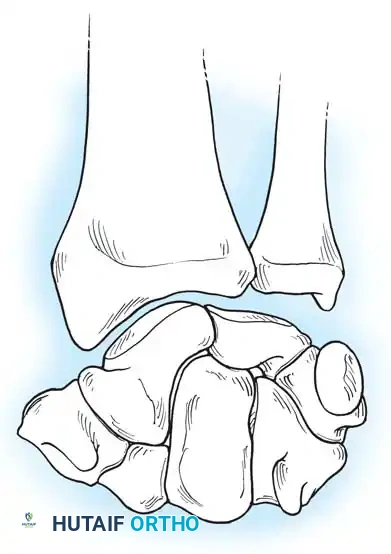

The osseous framework of the wrist comprises the distal radius, the distal ulna, and eight carpal bones arranged into two distinct rows.

The proximal carpal row consists of the scaphoid, lunate, triquetrum, and pisiform. This row acts as an intercalated segment; it has no direct tendinous insertions (with the exception of the flexor carpi ulnaris on the pisiform) and moves entirely in response to mechanical forces exerted by the surrounding articular contours and ligamentous tethers.

The distal carpal row includes the trapezium, trapezoid, capitate, and hamate. These bones are tightly bound to each other and to the metacarpal bases, forming a rigid functional unit that moves synchronously with the hand.

The radiocarpal joint is formed by the articulation of the biconcave distal radius (scaphoid and lunate fossae) with the convex proximal surfaces of the scaphoid and lunate. The triquetrum articulates proximally with the triangular fibrocartilage complex (TFCC) rather than the distal ulna directly.

Clinical Pearl: Viegas has emphasized the considerable anatomical variation found in the fourth carpometacarpal articulation, as well as the scaphotrapeziotrapezoid (STT), capitolunate, and hamatolunate articulations. Recognizing these morphological variants (e.g., a Type II lunate with a medial hamate facet) is critical, as they alter normal wrist kinematics and predispose patients to specific degenerative patterns, such as hamatolunate arthrosis.